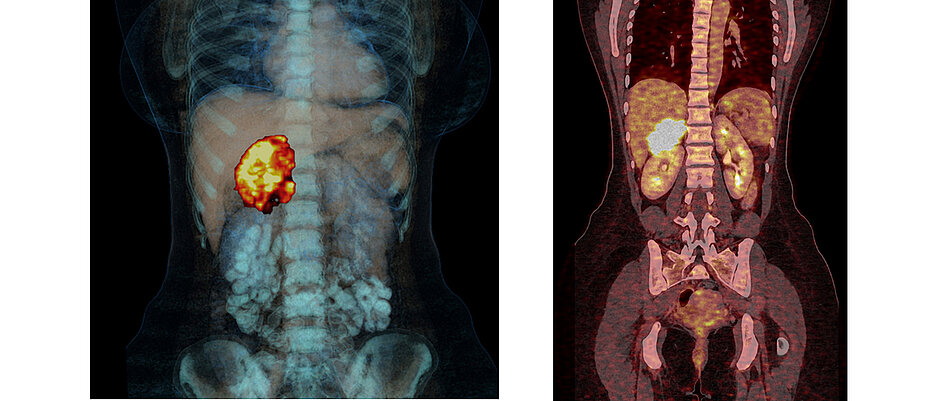

Nebennierenkrebs: Bei niedrigem Rückfallrisiko kein Mitotane

25.08.2023Nach der Entfernung eines Nebennierenkarzinoms ist nicht immer eine Folgetherapie mit Mitotane nötig. Das zeigen die Professoren Martin Fassnacht und Massimo Terzolo in einer klinischen Studie.

Schon die Diagnose sei schwierig, da das Nebennierenkarzinom sehr selten ist und anfänglich keine Symptome verursacht. Daher wird es oft erst im fortgeschrittenem Stadium entdeckt. In Deutschland gibt es schätzungsweise jedes Jahr etwa 80 bis 120 Neuerkrankungen. Je nach Art des Tumors kann operiert werden, im fortgeschrittenen Stadium sind zusätzlich eine Chemotherapie oder Bestrahlungen nötig.